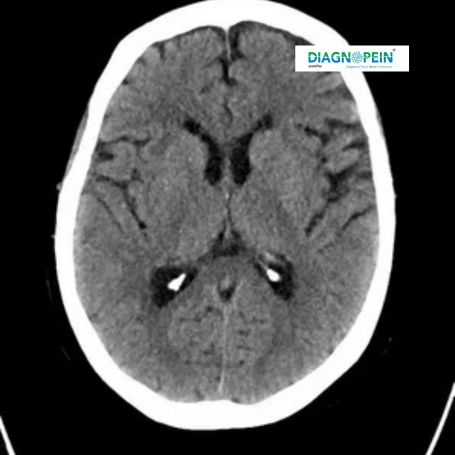

A CT Plain scan, also known as a non-contrast computed tomography, is a vital imaging test used to capture detailed cross-sectional images of the body without using any contrast dye. It helps doctors visualize internal organs, bones, blood vessels, and soft tissues accurately. At Diagnopein Nashik, our advanced CT scanners deliver high-resolution images that support quick and correct diagnosis for various medical conditions, including fractures, lung diseases, and brain injuries.

Proper placement during a CT Plain scan is crucial to achieving accurate and clear images for diagnosis. The positioning of the patient determines the clarity of internal structures shown in the scan. For example, correct head placement during a CT Brain Plain scan ensures better visualization of potential stroke signs or trauma effects. Similarly, for CT Chest Plain or CT Abdomen Plain, body alignment ensures reliable comparison between both sides of the body.

1. Detects a wide range of conditions from bone fractures to brain hemorrhages.